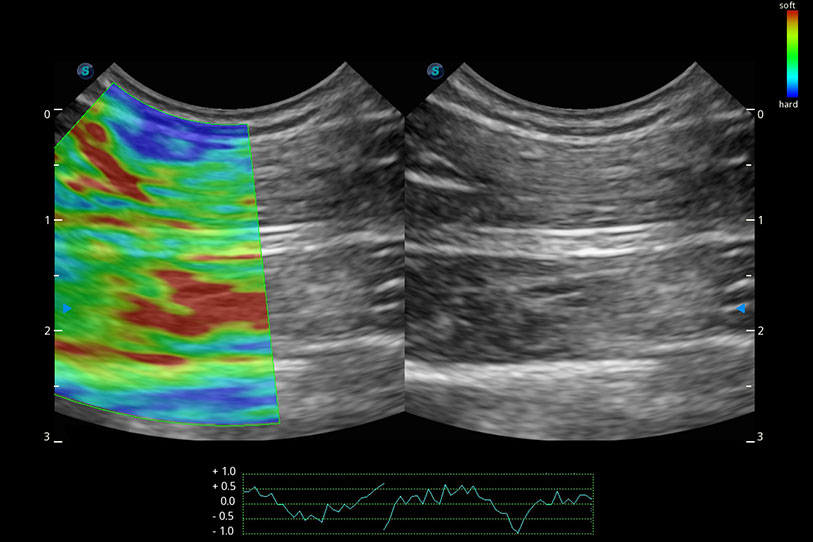

操作簡(jiǎn)便,無需高頻度外力作用即可真實(shí)反映組織的形變,快速評(píng)估腫瘤良惡性。